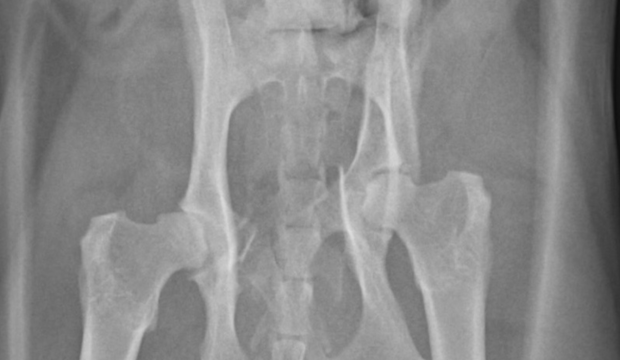

| 保護猫を自宅に迎え入れた際に、呼吸が荒いことに気づいたため当院を受診されました。レントゲン検査により、お腹の臓器が横隔膜(おうかくまく)をこえて心臓付近にまで脱出していることが判明しました。 |